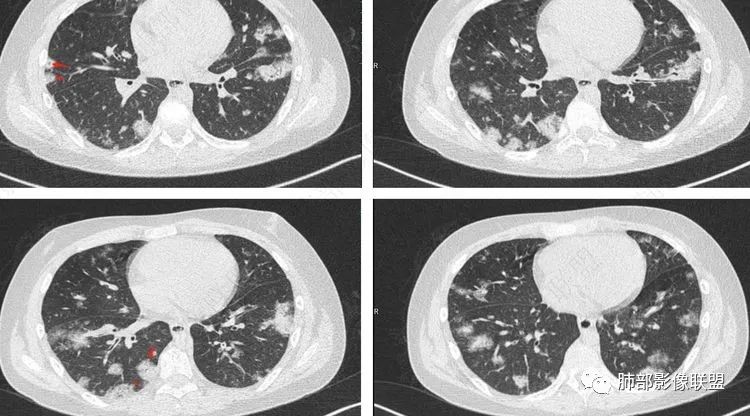

2.影像上肺多发混合密度片影,随机分布,胸膜下分布优势,病灶边界大多隐约可辨,偏柔和,动脉血管影穿行,未见钙化、液化空洞、或明确气囊影,未见树芽征。

血源性金黄色葡萄球菌性肺炎具有一些临床和影像学特征:

1.起病急,临床症状重;

2.表现多样,多种影像表现可同时出现,如斑片状影、小点状影、结节影、肺气囊等可在CT片上同时见到;

3.病灶比较广泛,多个肺野出现同时受累;

4.容易在短期内出现散在的肺气囊或多发的脓肿病灶;

5.病灶易变,短期内复查CT可见病灶的形态、部位、大小发生变化。

金黄色葡萄球菌肺炎CT征象 来源放射沙龙

一、影像特点

1.外围分布,胸膜下为主,两肺弥漫结节或胸膜下楔形影,边界清,周围伴有GGO

2.反晕征:往往紧贴胸膜,并且胸膜侧无环,周围GGO

3.空洞:分为两类。

第一类,偏心空洞,一侧壁厚,周围实变明显。

第二类,薄壁空洞(偏中后期):壁薄且均匀,内外壁光滑,张力高,内有气液平面、间隔影,各空洞相对独立互不相通

4.囊:张力高,壁薄,内外壁光滑,可有间隔

5.边缘收缩明显,结节密实,边缘收缩、凹陷,周围长索条影,提示吸收好转

6.胸腔积液、脓胸